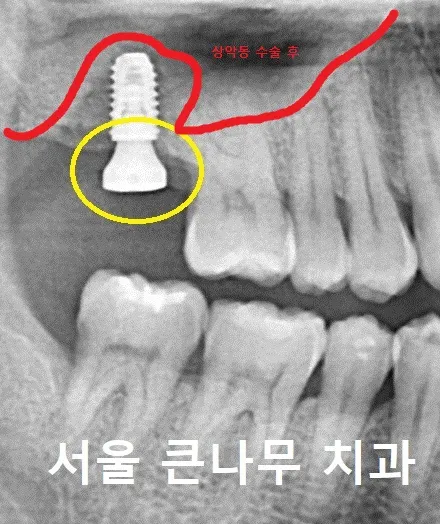

상악동 수술과 임플란트 수술 완료 후 사진입니다.

상악동을 들어 올려 공간을 확보해 준 후 뼈 이식을 해주어 임플란트를 식립할 수 있었습니다.

심어놓고 기다리는 4개월의 기간 동안 아래 치아가 위로 솟는 것을 방지하기 위해 치아 모양에 맞게 제작된 철사를 고정시켜줍니다.